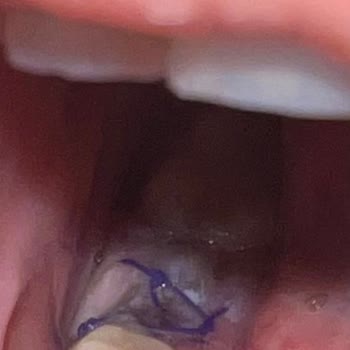

randevu-sistemi-hatasi-yuzunden-tedavim-gecikti-destek-alamadim-1.jpg